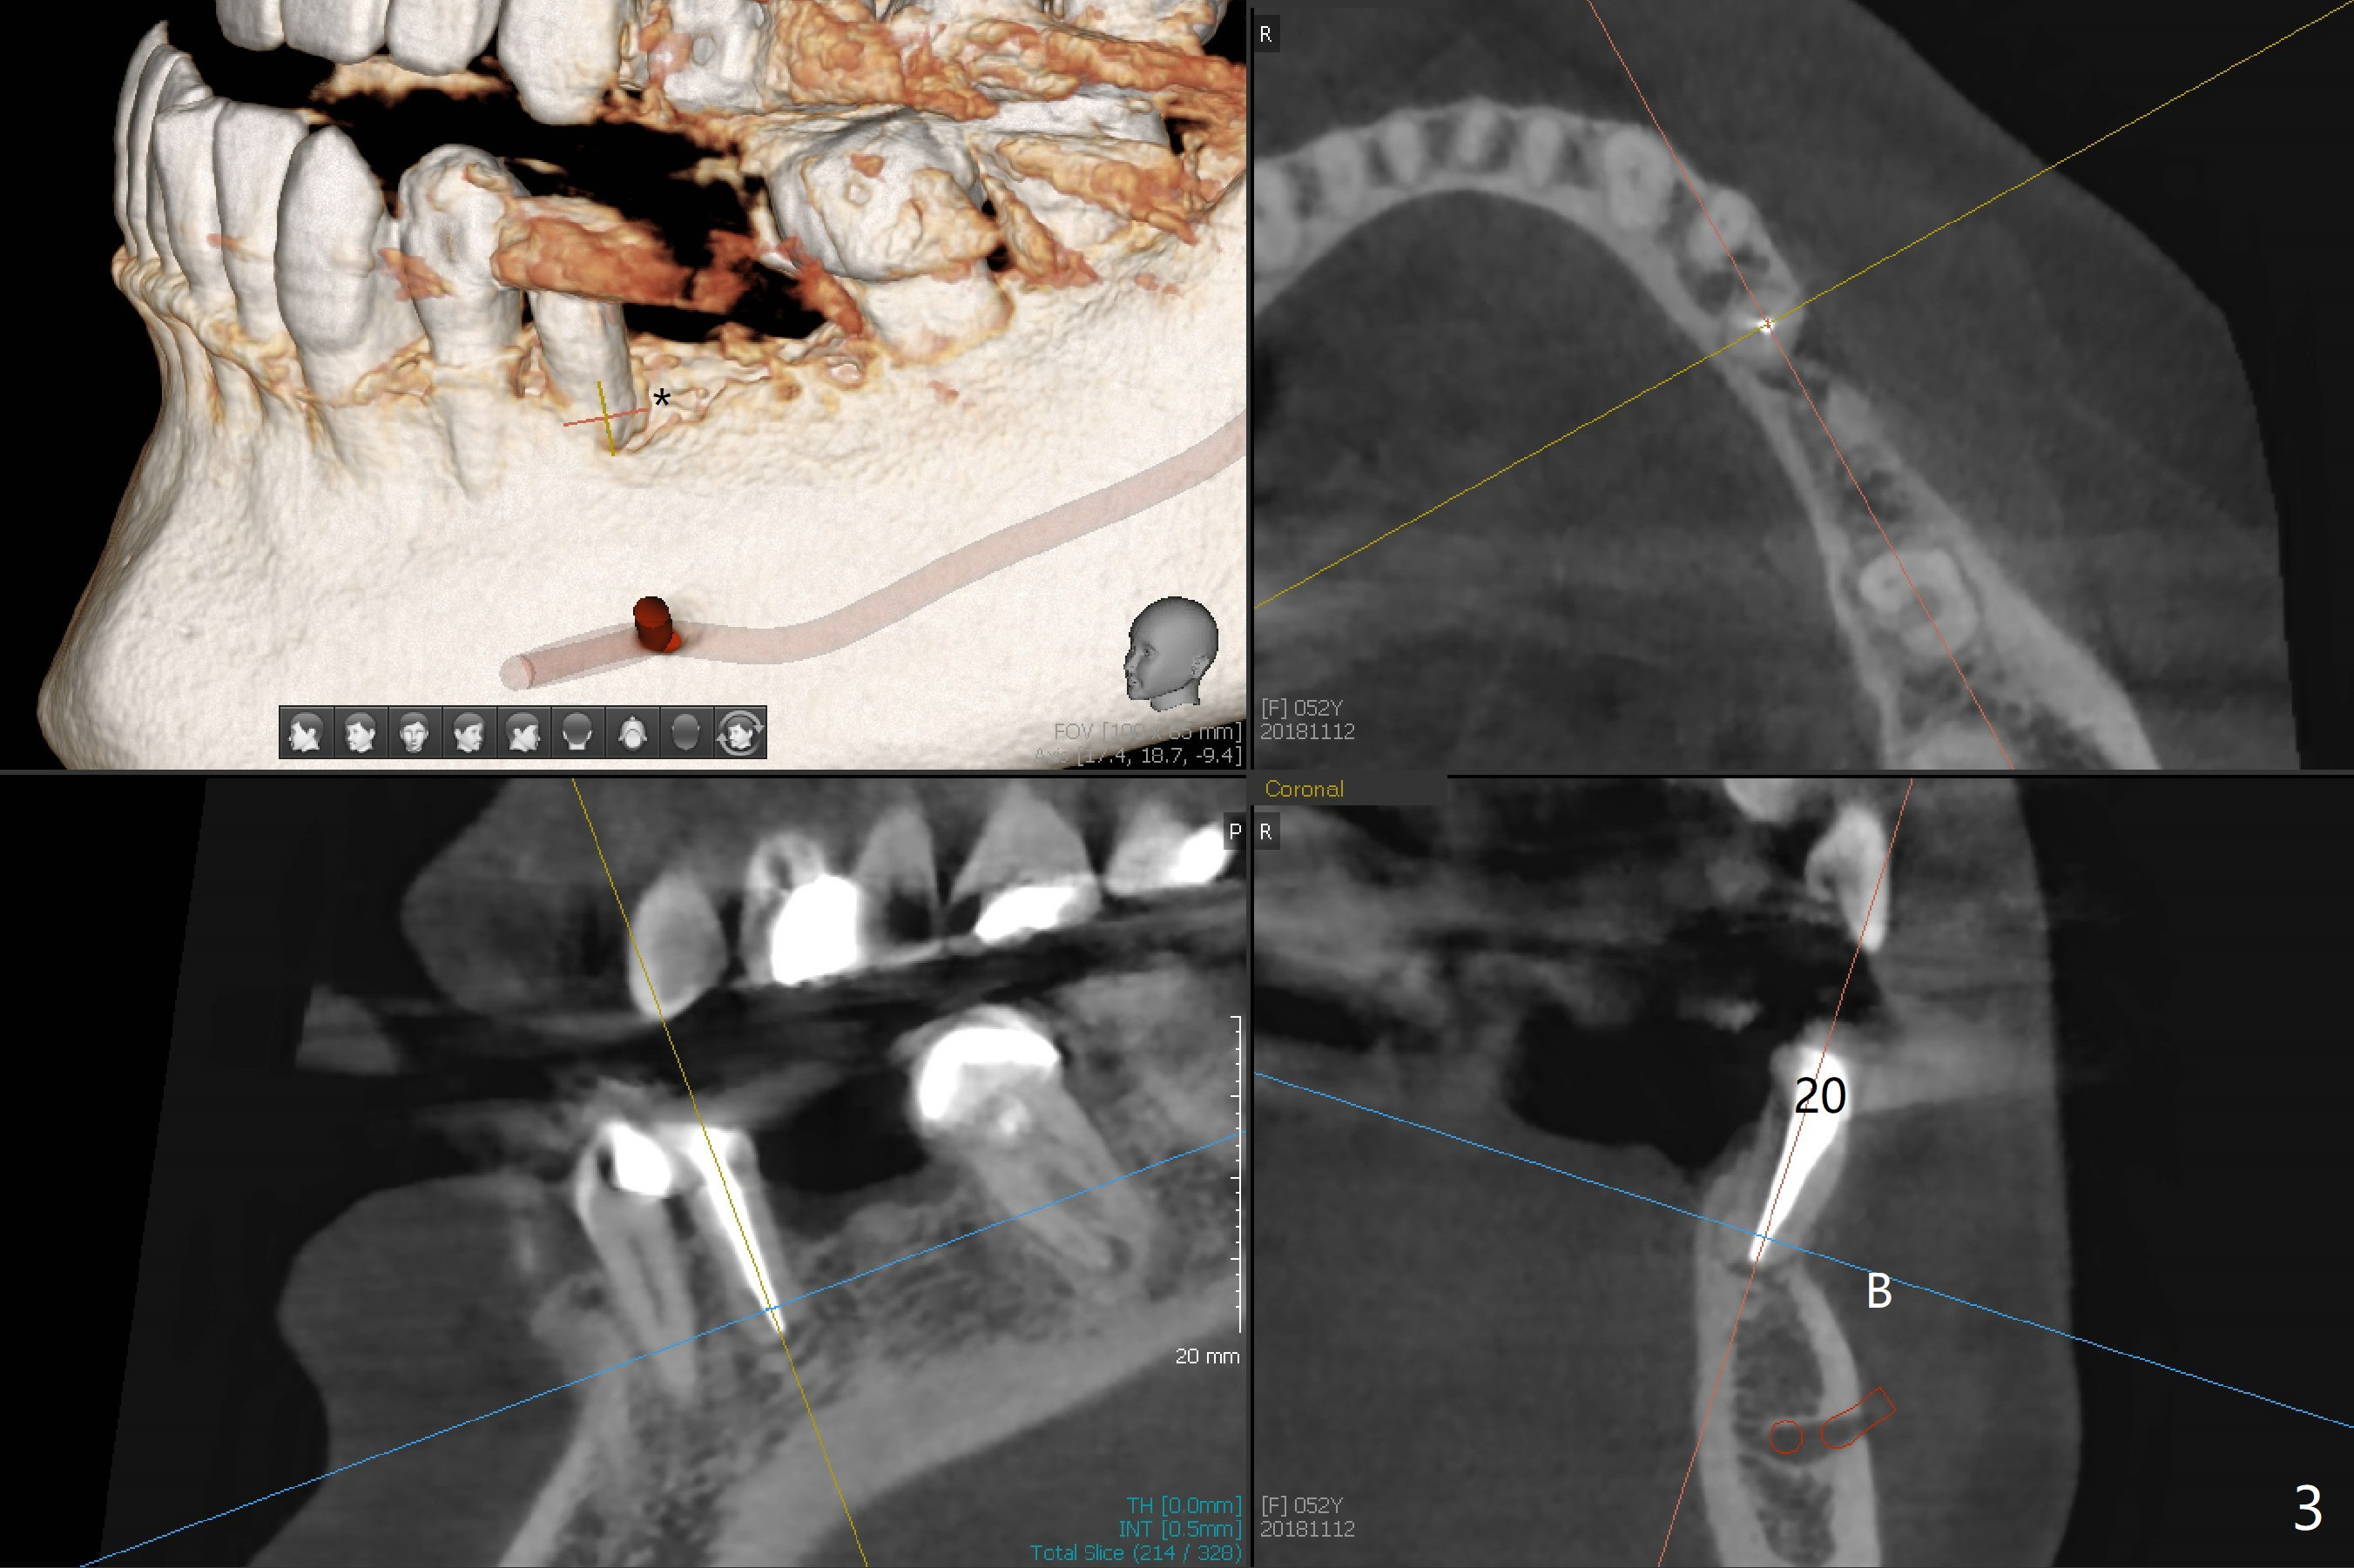

A 52-year-old woman requests an implant at #19 (Fig.1). Her other 2 concerns are the diastema between #5 implant crown and the tooth #6 (Fig.1 (^),2) and whether the tooth #20 is stable enough for crown after sectioning #18-20 FPD and RCT (Fig.1,3 (disto(*)-buccal (B) bone loss)). The ridge at #19 seems to be narrow; a 4x10 mm IS implant appears to be appropriate for the site (Fig.4). Since Magicore has a narrow core and aggressive fins, a 4.0 or 4.5x9(3) mm implant is apparently a good fit. After osteotomy, remove guide, use perio probe to determine crest level and place Magicore